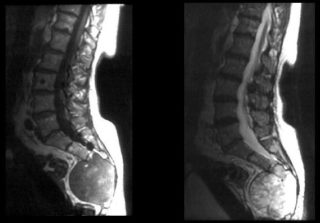

- КТ или МРТ при подозрении на метастазы;